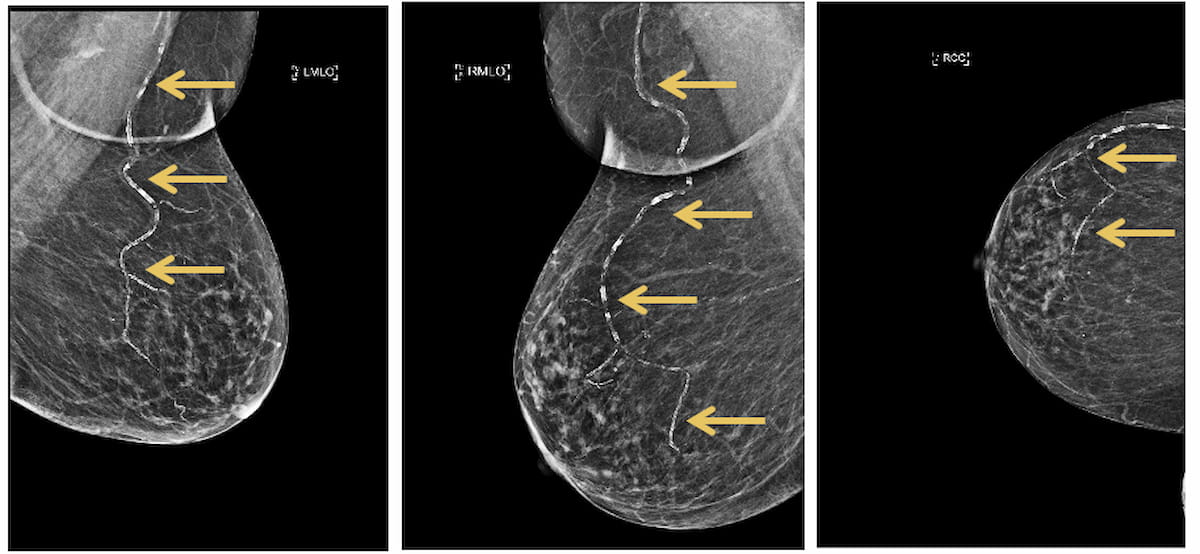

The Mammo Enhance Heart program combines AI detection of breast arterial calcification (BAC) on screening mammography and subsequent follow-up with a local network of cardiologists.

Emphasizing detection of breast arterial calcification (BAC) on screening mammograms, appropriate risk stratification for cardiovascular disease and timely follow-up with cardiologists, Radiology Partners has launched the Mammo Enhance Heart program.

In addition to utilizing FDA-cleared artificial intelligence (AI) to detect BAC on mammograms, Radiology Partners said the Mammo Enhance Heart program incorporates an internally developed scoring system for cardiovascular risk and facilitates follow-up with cardiology specialists.